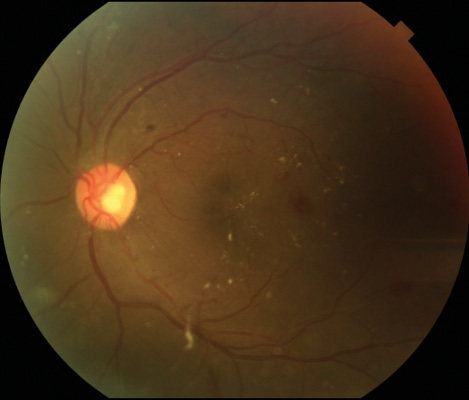

Standard macular fundus photography captures 30˚ of the posterior pole of the eye, including the macula and the optic nerve (Figure 1).2 Standard fundus cameras can collect seven fundus fields, which can be combined to create a montage showing a 75° field of view. Benefits of standard field color photography include ease of use, wide availability, and reproducibility.

Figure 1. Standard 30 ̊ photo of an eye with DR.

One limitation of fundus photography is that it cannot confirm clinically significant macular edema (CSME). This is an examination finding diagnosed by fundus biomicroscopy with one of three criteria: hard exudates within 500 µm of the fovea with associated retinal thickening; retinal thickening within 500 µm of the fovea; or an area of retina thickening more than 1500 µm in diameter that is less than 1500 µm from the fovea.3 Other limitations of standard fundus photography include decreased quality of imaging in the presence of media opacity, lack of fine retinal detail, and poor visualization of the peripheral retina.